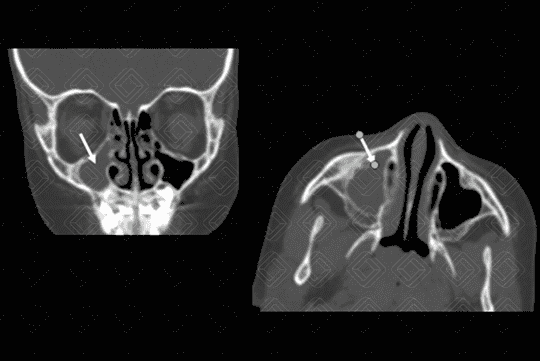

Texto alternativo para a imagem Figura 3. Créditos: Dra Elazir Mota - Rio de Janeiro/RJ

Descrição da lesão: Tomografia computadorizada de seios da face com cortes axiais, seguida de reconstruções coronais. Preenchimento completo do seio maxilar direito (seta branca na figura 1) e parcial das células etmoidais bilateralmente (setas vermelhas na figura 2), associado à obliteração do infundíbulo deste lado. Observa-se, ainda, espessamento mucoso concêntrico do seio esfenoidal esquerdo (asterisco na figura 3).